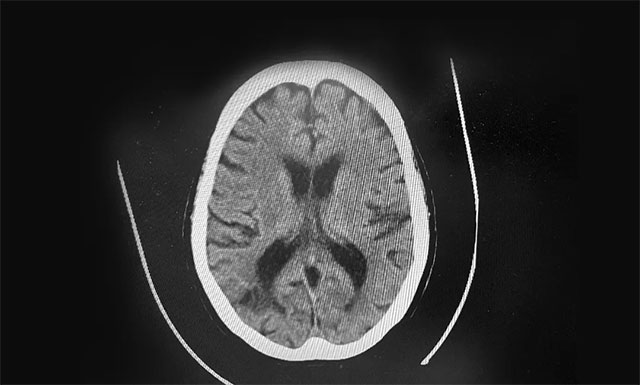

▲ 根據(jù)急診CT影像結果,排除患者腦出血

19:37 患者頭部CT檢查完成,影像科3分鐘出報告,CT報告排除患者腦出血。根據(jù)影像學檢查結果,并結合其病史,張琪主任判斷患者為急性腦梗,發(fā)病時間為18:00分左右,還處于靜脈溶栓治療4.5小時的時間窗內(nèi),有溶栓治療指征,可溶栓治療,積極治療血管有再通希望。